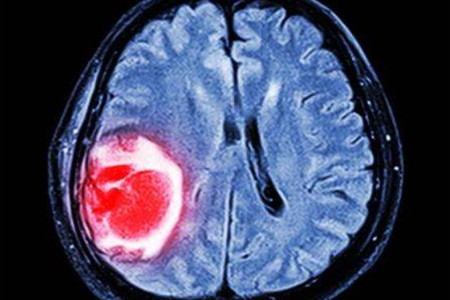

腦瘤是一種在顱内形成的腫瘤,它可以是良性的,也可以是惡性的。随着醫學科技的進步,腦瘤的診斷和治療都有了顯著的改進。

腦瘤是一種發生在大腦内部的腫瘤,它可以影響大腦的正常功能,從而影響患者的健康和生活質量。腦瘤的形成原因尚不完全清楚,但可能與遺傳、環境因素等有關。

腦瘤可以根據其組織學特性分爲良性腫瘤和惡性腫瘤。良性腫瘤通常生長緩慢,邊界清晰,不會擴散到其他部位,常見的良性腫瘤有腦膜瘤、垂體瘤等。惡性腫瘤生長迅速,邊界不清,容易擴散,常見的惡性腫瘤有膠質瘤、淋巴瘤等。